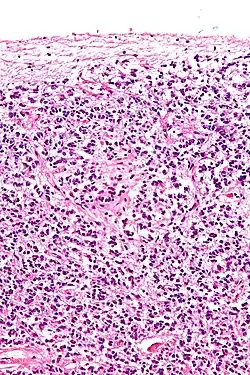

Os pinealócitos são as principais células da glândula pineal e são responsáveis pela produção e secreção de melatonina, um hormônio importante na regulação dos ritmos circadianos.[1] Esse tipo de célula possui uma organela chamada de fita sináptica, esta é considerada um marcador específico para pinealócitos. Algumas das enzimas do pinealócitos incluem 5-HT N-acetil transferase e 5-hidroxiindole-O-metiltransferase, que são utilizados para converter a serotonina em melatonina.

Os pinealócitos secretam melatonina em seus capilares através de longos processos citoplasmáticos que lembram os axônios dos neurônios. A secreção de melatonina é estimulada pela inervação simpática do gânglio cervical superior. Eles também têm processos citoplasmáticos mais curtos que se conectam com pinealócitos adjacentes via desmossomos.

Pinealócitos têm grandes núcleos irregulares com nucléolos proeminentes.